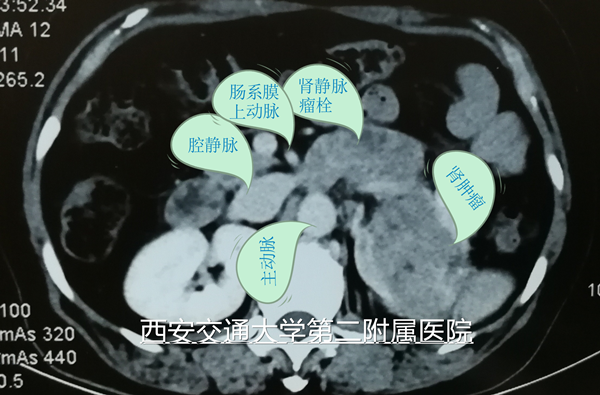

2018年5月18日,西安交通大学第二附属医院泌尿外科成功完成一例经腹膜后腔镜左肾并肾静脉瘤栓根治性切除术。该病例患者为中年女性,以血尿20余天主诉入院,入院检查发现左肾有直径约10cm肿瘤,同时左肾静脉有瘤栓形成,瘤栓近端超越肠系膜上动脉水平,接近下腔静脉。入院检查未发现远处转移征象。根据循证医学证据,如能够成功进行左肾根治并瘤栓切除 ,将显著延长患者生存期、甚至达到治愈水平。

5月18日手术当天,麻醉科吕建瑞主任、李卫松医生,手术室吴莉娜、孙楠与主管医生李洪亮再次沟通,明确手术难点、风险、注意事项以及术中可能用到的各项特殊用品。手术由李洪亮副主任医生主刀、李刚主治医生一助、住陪医生尉博、赵阿孟辅助,种铁主任对该手术非常重视,全程台下进行指导,及时指出术中的注意事项。术中通过合理设计、精细解剖、充分显露左肾静脉与主动脉、肠系膜上动脉,最终顺利按计划通过左侧腹膜后入路腔镜下完成手术。术中无明显出血,麻醉复苏顺利,手术当晚查房患者精神状态非常好,术后第一天患者已经下地活动,肠功能恢复,并开始正常饮食。目前患者恢复顺利,患者及家属对我院的医疗技术水平表示非常满意。